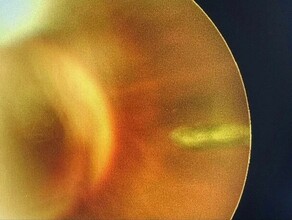

В Приморье в больницу обратился мужчина после работы с шлифовальной щёткой – металлическая щетинка попала ему в глаз. Обследование показало, что инородное тело прошло внутрь глаза и остановилось в нескольких миллиметрах от важных структур.

«Пациенту повезло – щетинка застряла в относительно безопасной зоне, что позволило избежать тяжёлых осложнений», – отметил врач-офтальмолог Краевой клинической больницы №2 Максим Богданец.

Врачи провели операцию: аккуратно удалили инородное тело и ушили повреждение. После вмешательства назначили лечение, чтобы предотвратить воспаление, которое может привести к потере зрения. Сейчас пациент идёт на поправку, осложнений не выявлено, сообщается в паблике учреждения.